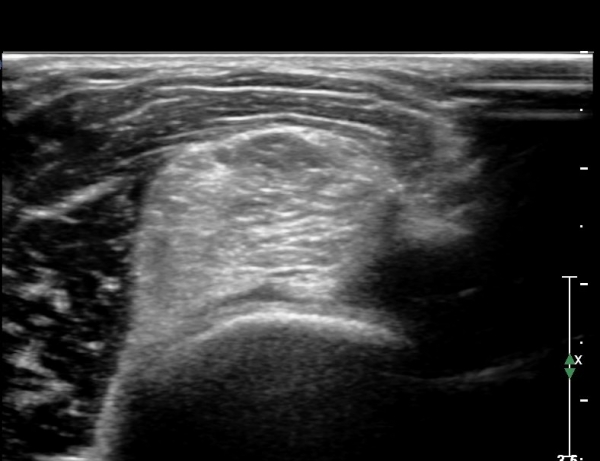

ŽÃËÀÚ¸¦ Á¶±Ý ´õ ¸»´ÜÀ¸·Î À̵¿ÇÏ´Ï ¿ä°ñ ¸öÅëÀÌ °üÂûµÇ°í ÀÌÁú¼º°í¿¡ÄÚ Á¾±«¿Í Èİñ°£½Å°æ ºÎÁ¾ÀÌ °ýÂûµÊ(»çÁø 3).